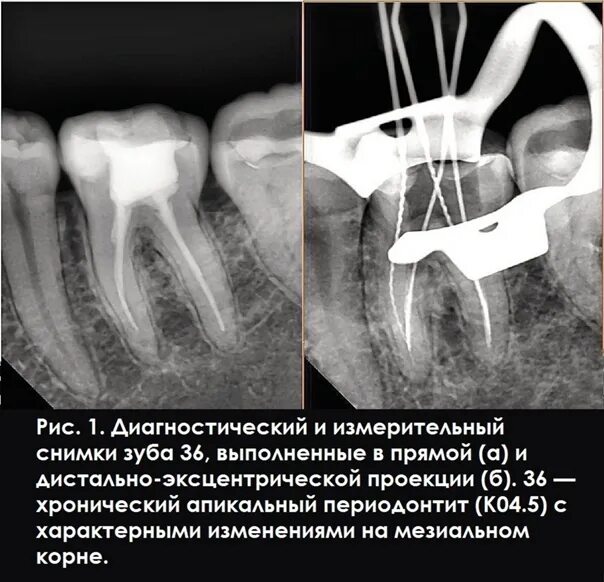

Как понять снимок зуба